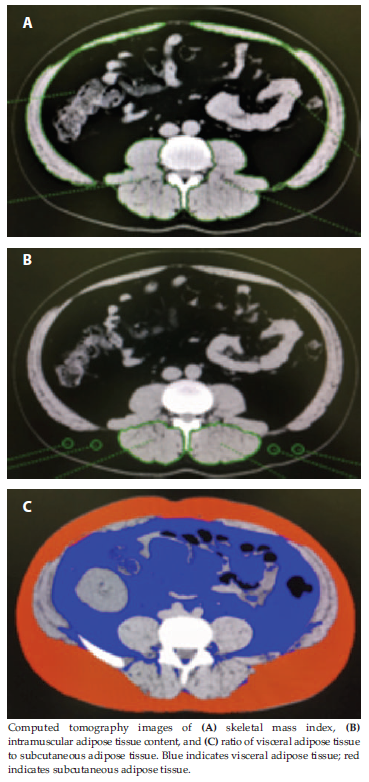

The SMI was calculated using the skeletal muscle area at the L3 level assessed by manual tracing with AZE Virtual Place software (Figure 1A), where SMI is the cross-sectional area of all skeletal muscle in centimeters squared divided by the height in meters squared. The skeletal muscles at the L3 level were as follows: rectus abdominis muscle, external oblique muscle, internal oblique muscle, transversus abdominis muscle, psoas major muscle, quadratus lumborum muscle, erector spinae muscle, latissimus dorsi muscle, and multifidus lumborum muscle (Figure 1A). The IMAC value represents muscle quality. Higher IMAC values indicate greater deterioration of muscle quality. The IMAC value was calculated with L3-level CT cross-sectional images, with IMAC equal to the mean CT attenuation value (measured in Hounsfield units [HU]) in the region of interest of multifidus muscle divided by the mean CT attenuation value in the region of interest of subcutaneous fat (Figure 1B). The VAT-to-SAT ratio (VAT/SAT) was also calculated with cross-sectional umbilical-level CT images (Figure 1C). Subcutaneous adipose tissue was defined as the extraperitoneal fat between skin and muscles with CT attenuation values within the range from -190 to -50 HU on 1 of the constructed images. Visceral adipose tissue was defined by intraperitoneal fat with the same density as the SAT layer. Segmentation of abdominal SAT and VAT areas was determined using AZE Virtual Place software. Higher values indicate lower quality fat distribution.

Figure 1. Body Composition Analysis With Cross-Sectional Computed Tomography Images